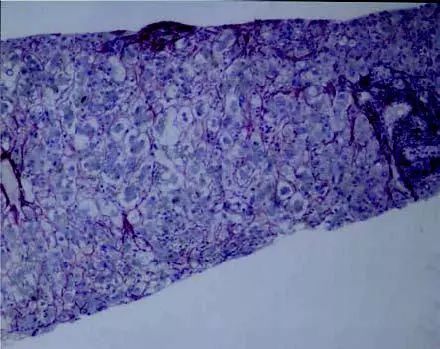

3. AFLP的病理学特征

AFLP的经典病例特征为:肝总体结构未改变,肝细胞内微泡型脂肪浸润、肿胀;细小的脂肪滴围绕细胞核分布,因而胞质呈泡沫状。

图1 一例AFLP患者的病理切片1(来源:见参考文献[3])

虽然肝脏活检是金标准,但由于需要及时治疗,且活检为有创检查,故很少进行活检。